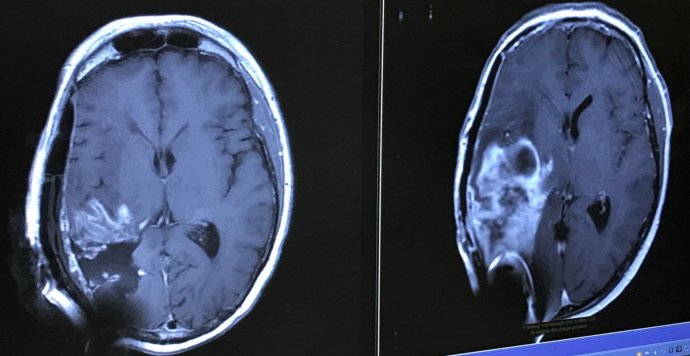

That last observation was odd. I called my sister-in-law who is a physician. She asked me to dial 911. Twelve hours later Hargobind was in back to back surgeries for ten hours to remove a golf ball sized tumor from the right half of his brain.

The diagnosis was terminal brain cancer. Hargobind will go through eight surgeries to remove tumor re-growth, add a shunt to drain fluids from his brain to the stomach and have a artificial skull inserted. One of these surgeries last year included a trial therapy utilizing an injection in the brain. He came out of surgery without the use of the left side of the body.